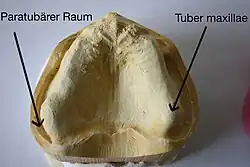

Nur noch in seltenen Ausnahmefällen werden eine Tuberanästhesie (am Oberkieferhöcker, Tuber maxillae), eine Schädelbasisanästhesie, eine perkutane Leitungsanästhesie im Gesicht, eine extraorale Leitungsanästhesie, eine intraossäre Anästhesie, eine intraseptale Anästhesie oder die Ausschaltung des Nervus infraorbitalis durchgeführt. Die Kälteanästhesie wird wegen der schleimhautschädigenden Wirkung kaum angewandt. Die zentrale Anästhesie des Nervus trigeminus durch eine Blockade am Ganglion Gasseri (Ganglion semilunare) erfolgt nur noch bei schwer beherrschbaren Schmerzzuständen bei einer Trigeminusneuralgie. Sie erfolgt in der Regel durch den Neurochirurgen unter röntgenologischer Kontrolle.

Die Gow-Gates-Technik (benannt nach dem Erstbeschreiber, dem Australier George Gow-Gates) wurde 1973 entwickelt, um die Misserfolgsquote der Leitungsanästhesien auf nur 5 % zu vermindern. Mittels einer einzigen Injektion werden mehrere Leitungsanästhesien, nämlich des Nervus alveolaris inferior, des Nervus lingualis, des Nervus mylohyoideus, des Nervus auriculotemporalis und – mit 75-prozentiger Wirkung – auch des Nervus buccalis, durchgeführt. Hierzu wird ein Depot des Lokalanästhetikums am Kondylenhals des Unterkiefers gesetzt.[51] Bei weit geöffnetem Mund wird an der Incisura intertragica der Kondylenkopf ertastet und dient als „Zielmarke“. Die Injektionsnadel (Gaugegröße 27) wird zu zwei Dritteln in die Umschlagfalte hinter dem Tuber maxillae in den paratubären Raum eingeführt und der Knochenkontakt am Kondylenhals gesucht. Der Nervenstrang selbst liegt distal des Kondylus. Nach Aspirationstest und erfolgter Injektion soll der Patient den Mund eine weitere Minute weit geöffnet halten. Wegen der geringen vaskulären Versorgung dieses Bereichs und des dadurch verlangsamten Abtransports des Lokalanästhetikums wird ein Lokalanästhetikum (Mepivacain – Scandicain, Meaverin) ohne Vasokonstriktor verwendet. Die Injektion ist für den Patienten kaum wahrnehmbar.[52] Der Patient sollte zuvor aufgeklärt werden, dass bei der Gow-Gates-Lokalanästhesie eine Gesichtshälfte mehr oder minder vollständig anästhesiert sein wird.

Paratubärer Raum

Paratubärer Raum -